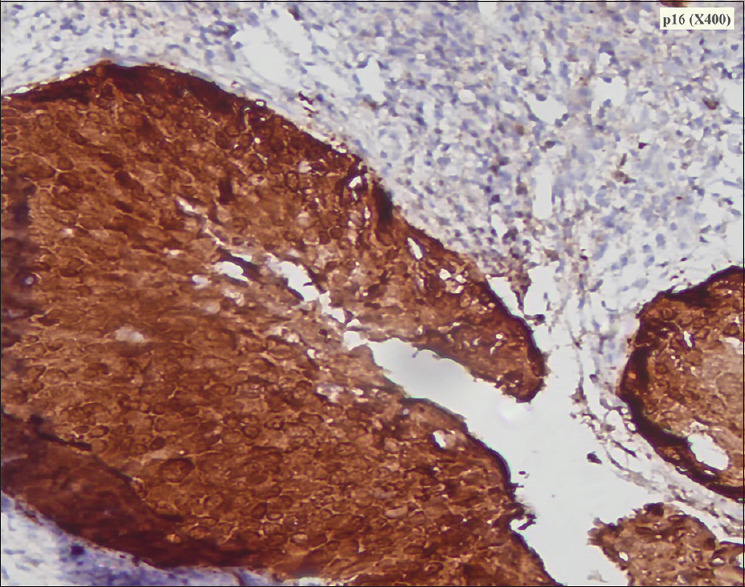

摘要浅表性宫颈鳞状细胞癌(SCC)是一种罕见的疾病,文献报道的病例很少。本病例报告简要介绍了绝经后妇女浅表性宫颈鳞状细胞癌的发现。65岁绝经后妇女,阴道出血1-2个月。经检查,子宫颈健康,无明显生长。她在磁共振成像上被诊断为子宫内膜恶性肿瘤。在子宫内膜和宫颈活检中,组织病理学显示宫颈外宫颈上皮内瘤变III型伴宫颈内膜和子宫内膜鳞状细胞癌。患者行改良根治性子宫切除术并双侧盆腔淋巴结切除术,组织病理学显示宫颈SCC浅表扩散,肿瘤细胞累及子宫内膜、子宫肌层、输卵管旁、卵巢旁、阴道边缘(未扩散至盆腔)和主动脉旁淋巴结。患者通过辅助放化疗得到了进一步的成功治疗。宫颈鳞状细胞癌是一种非常罕见的现象。它的传播不仅限于子宫内膜,而且可以扩展到子宫肌层、输卵管旁组织、卵巢旁组织和阴道组织。

Superficial spreading cervical squamous cell carcinoma (SCC) is a rare phenomenon with few cases reported in the literature. The present case report briefs the findings of superficial spreading cervical SCC in postmenopausal women. A 65-year-old postmenopausal woman presented with bleeding per-vaginum for 1-2 months. On examination, the cervix was healthy with no visible growth. She was diagnosed with an endometrial malignancy on magnetic resonance imaging. On endometrial and cervical biopsy, histopathology revealed cervical intraepithelial neoplasia III in ectocervix with SCC in endocervical and endometrial curetting. The patient underwent modified radical hysterectomy with bilateral pelvic lymphadenectomy and histopathology revealed superficially spreading cervical SCC with tumor cells involving endometrium, myometrium, paratubal, paraovarian, vaginal margins without extending to pelvic, and para-aortic lymph nodes. The patient was further managed successfully with adjuvant chemoradiotherapy. Superficial spreading cervical SCC is very rare phenomenon. Its spread is not only limited to endometrium but can extend to involve myometrium, paratubal, paraovarian, and vaginal tissues.